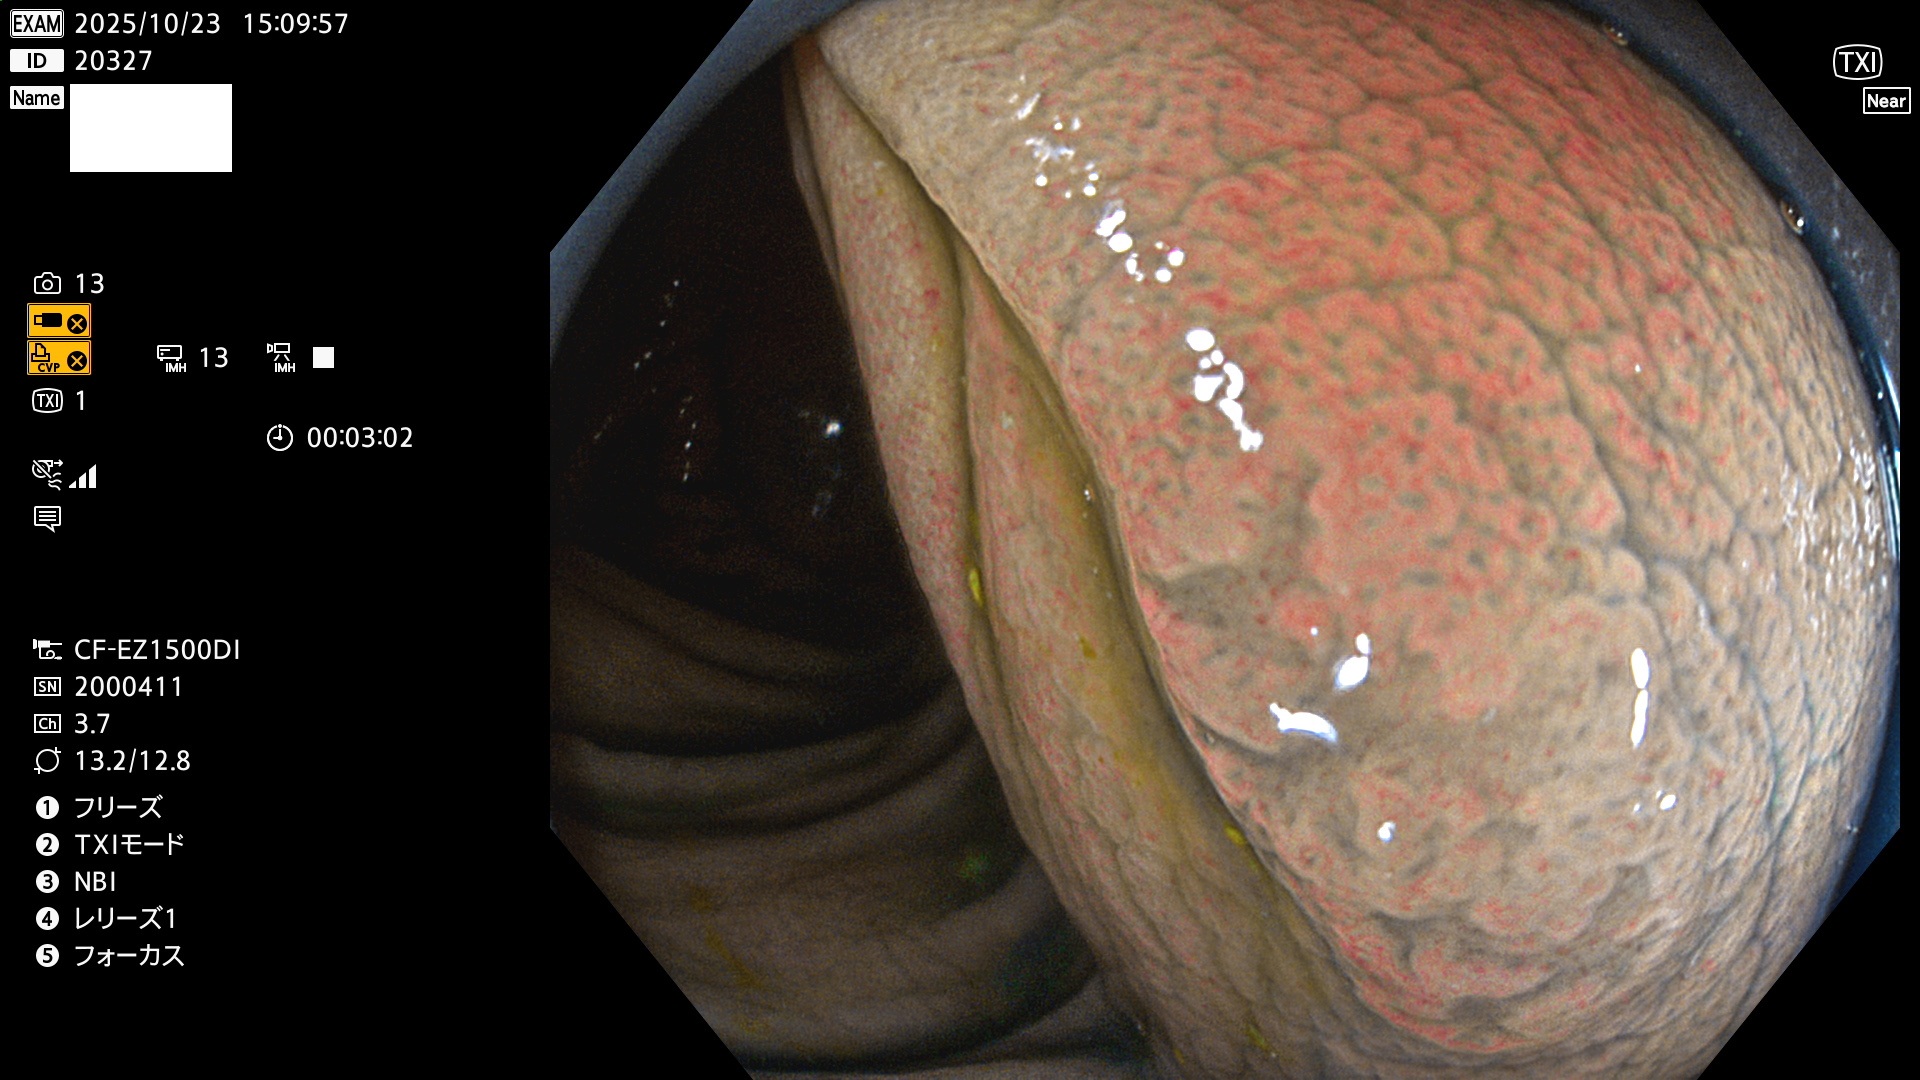

完全に平坦な物をUb、陥凹している物をUcと呼びます。Ubは認識が困難で、Ucはびらん(炎症)と紛らわしいために見落とされやすく、「内視鏡後・大腸癌」の原因になります。

専門的)Uc=De Novo癌? 内視鏡の解像度が低かった時代、このような説もありました。しかし今日の高精度内視鏡では良性の微小なUc型腺腫(APC遺伝子異常の腺腫)が日常的に見つかります。Ucこそが多段階発癌(Adenoma-Carcinoma Sequence)のMain Routeです。

毎週の検査(木・金・土・日)に発見されたUbとUc型・腺腫を、その週の日曜の夜にUPし1週間、提示します。

写真公開の目的は「透明性・信憑性の担保」ですが、公開を希望されない方はメールで御連絡下さい。直ちに削除いたします。

2025年10月23日〜10月26日の4日間(40件)で6個 (Uc_ADR=6個/40人=15%)